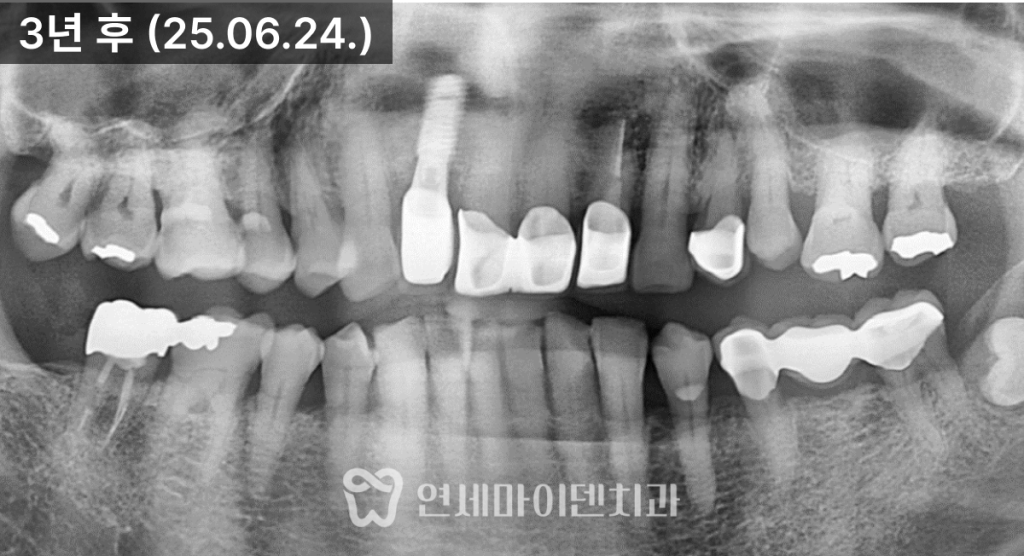

치료 후 3년이 지난 현재까지도

안정적으로 유지되고 있습니다.

임플란트로 치료한 앞니는

안정적으로 자리 잡았고,신경치료를 시행한 치아는

치근단 낭성 병변이

자연스럽게 치유되면서

추가적인 치근단 수술 없이

회복을 확인할 수 있었습니다.